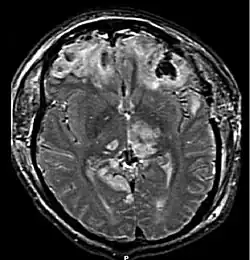

MRI showing injury due to brain herniation | |

Brain herniation is a potentially deadly side effect of very high pressure within the skull that occurs when a part of the brain is squeezed across structures within the skull. The brain can shift across such structures as the falx cerebri, the tentorium cerebelli, and even through the foramen magnum (the hole in the base of the skull through which the spinal cord connects with the brain). Herniation can be caused by a number of factors that cause a mass effect and increase intracranial pressure (ICP): these include traumatic brain injury, intracranial hemorrhage, or brain tumor.[1]

Treatment involves removal of the etiologic mass and decompressive craniectomy. Brain herniation can cause severe disability or death. In fact, when herniation is visible on a CT scan, the prognosis for a meaningful recovery of neurological function is poor.[2] The patient may become paralyzed on the same side as the lesion causing the pressure, or damage to parts of the brain caused by herniation may cause paralysis on the side opposite the lesion.[11] Damage to the midbrain, which contains the reticular activating network which regulates consciousness, will result in coma.[11] Damage to the cardio-respiratory centers in the medulla oblongata will cause respiratory arrest and (secondarily) cardiac arrest.[11] Investigation is underway regarding the use of neuroprotective agents during the prolonged post-traumatic period of brain hypersensitivity associated with the syndrome.[17]